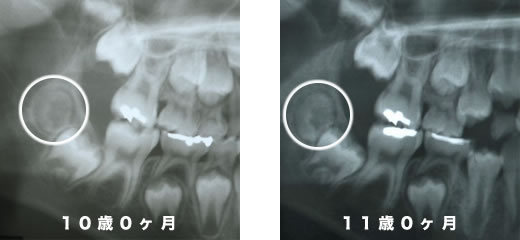

以下の症例は、12歳時に親知らず(第三大臼歯)を抜歯し、矯正装置を使うことなく第二大臼歯が正しい位置に誘導されて、上下の歯が咬み合うことができました。

- 診断名あるいは主な症状:第三大臼歯が第二大臼歯を圧迫して萌出を妨げている、叢生

- 年齢:10歳

- 治療に用いた主な装置:使用無し(経過観察のみ)

- 抜歯部位:第三大臼歯

- 治療期間:5年11か月(経過観察期間を含む)

混合歯列期のお子様の咬み合わせを診る上で、同時に生え変わりの様子にも気を配ることはとても重要です。

乳歯の抜けた時期、それと交換する永久歯が生えてきた時期、レントゲン診査での乳歯の歯根吸収の状態や、永久歯の歯根の完成程度、さらに乳歯と永久歯の位置関係はどうなっているか、理想的な生え変わりが行われれば、(遺伝的要素や、歯の過不足そして歯の形の問題を除けば)それだけでも歯は自然に良い方向に生えてこようとします。

今回の症例では親知らずが奥歯を圧迫し始めたため12歳時に抜歯を行いました。結果、第2大臼歯が正しい位置に誘導されて生えています。もし、抜歯を先延ばしにしていたとしたらどうなったと思いますか?